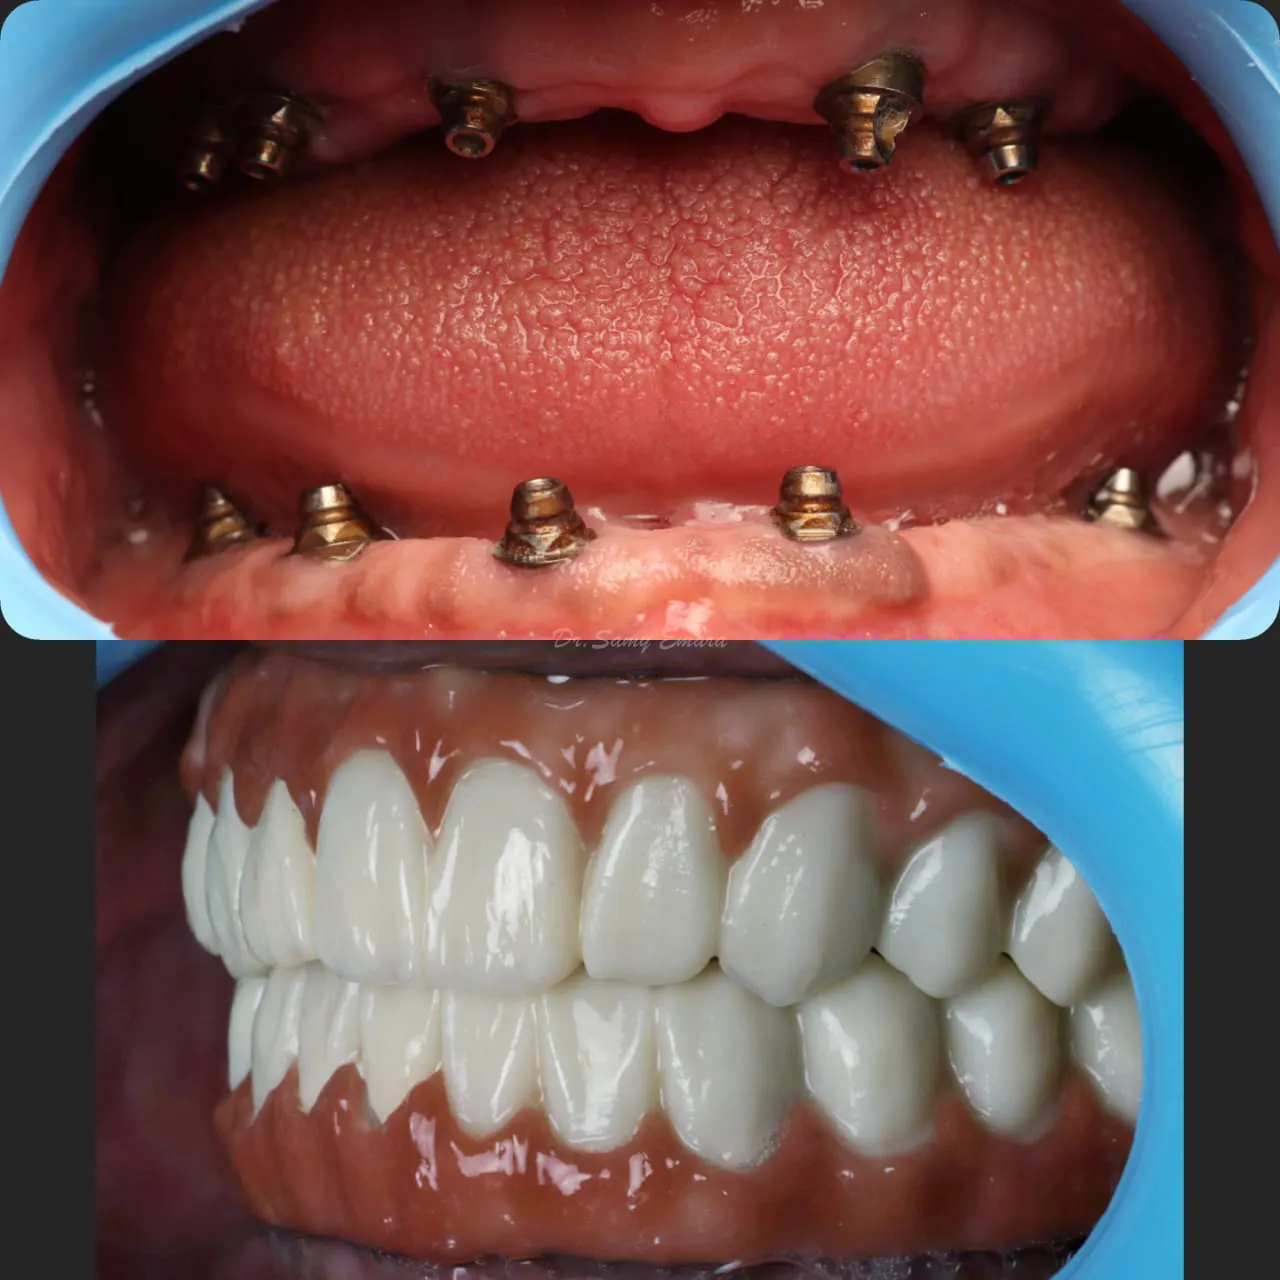

Full Mouth Reconstruction

Implant